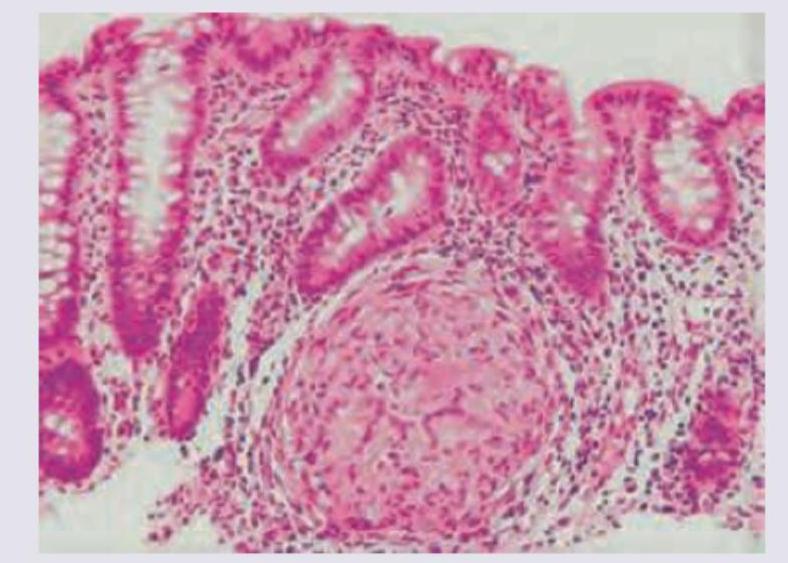

Question 6: A 50-year-old male presents with colicky abdominal pain and recurrent bloody diarrhea. Colonoscopy shows geographical ulcers. Histopathology is shown below. Diagnosis is:

- B. Inflammatory bowel disease (Correct Answer)

Explanation: ***Inflammatory bowel disease*** - The presentation of **colicky abdominal pain**, **recurrent bloody diarrhea**, and **geographical ulcers** on colonoscopy are classic features of **Inflammatory Bowel Disease (IBD)**, specifically **Crohn's disease** [1]. - Histopathology in Crohn's disease often shows **transmural inflammation**, **non-caseating granulomas**, and **crypt abscesses**, which align with the clinical picture [1,2]. *Pseudomembranous colitis* - This condition is typically caused by **Clostridium difficile infection** and presents with watery diarrhea, fever, and abdominal pain, often after antibiotic use. - Colonoscopy reveals **yellowish-white plaques (pseudomembranes)**, not geographical ulcers. *NHL (Non-Hodgkin Lymphoma)* - While NHL can affect the colon, it usually presents with symptoms like **abdominal mass**, weight loss, and less commonly with recurrent bloody diarrhea as the primary symptom. - Colonoscopy findings would typically show a **mass lesion** or **polypoid growths**, not geographical ulcers. *Adenocarcinoma colon* - **Adenocarcinoma of the colon** is more common in older adults and typically presents with changes in bowel habits, rectal bleeding, and weight loss. - Colonoscopy would reveal a **polypoid mass** or an **ulcerative lesion** that is often solitary and malignant, not widespread geographical ulcers. **References:** [1] Cross SS. Underwood's Pathology: A Clinical Approach. 6th ed. Common Clinical Problems From Alimentary System Disease, pp. 365-367. [2] Kumar V, Abbas AK, et al.. Robbins and Cotran Pathologic Basis of Disease. 9th ed. The Gastrointestinal Tract, pp. 806-807.